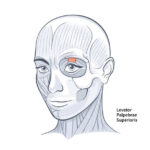

ATL-119 LOCAL ANESTHESIA TRAINING KIT SOFT